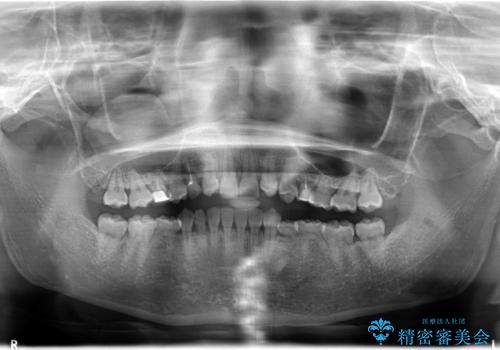

- 後続永久歯が欠損した患者様です。

矯正治療にて歯並びを改善したのち、インプラントにて咬合回復を行う治療計画としました。

捻転が強い部分だけはワイヤーの部分矯正で対応しております。